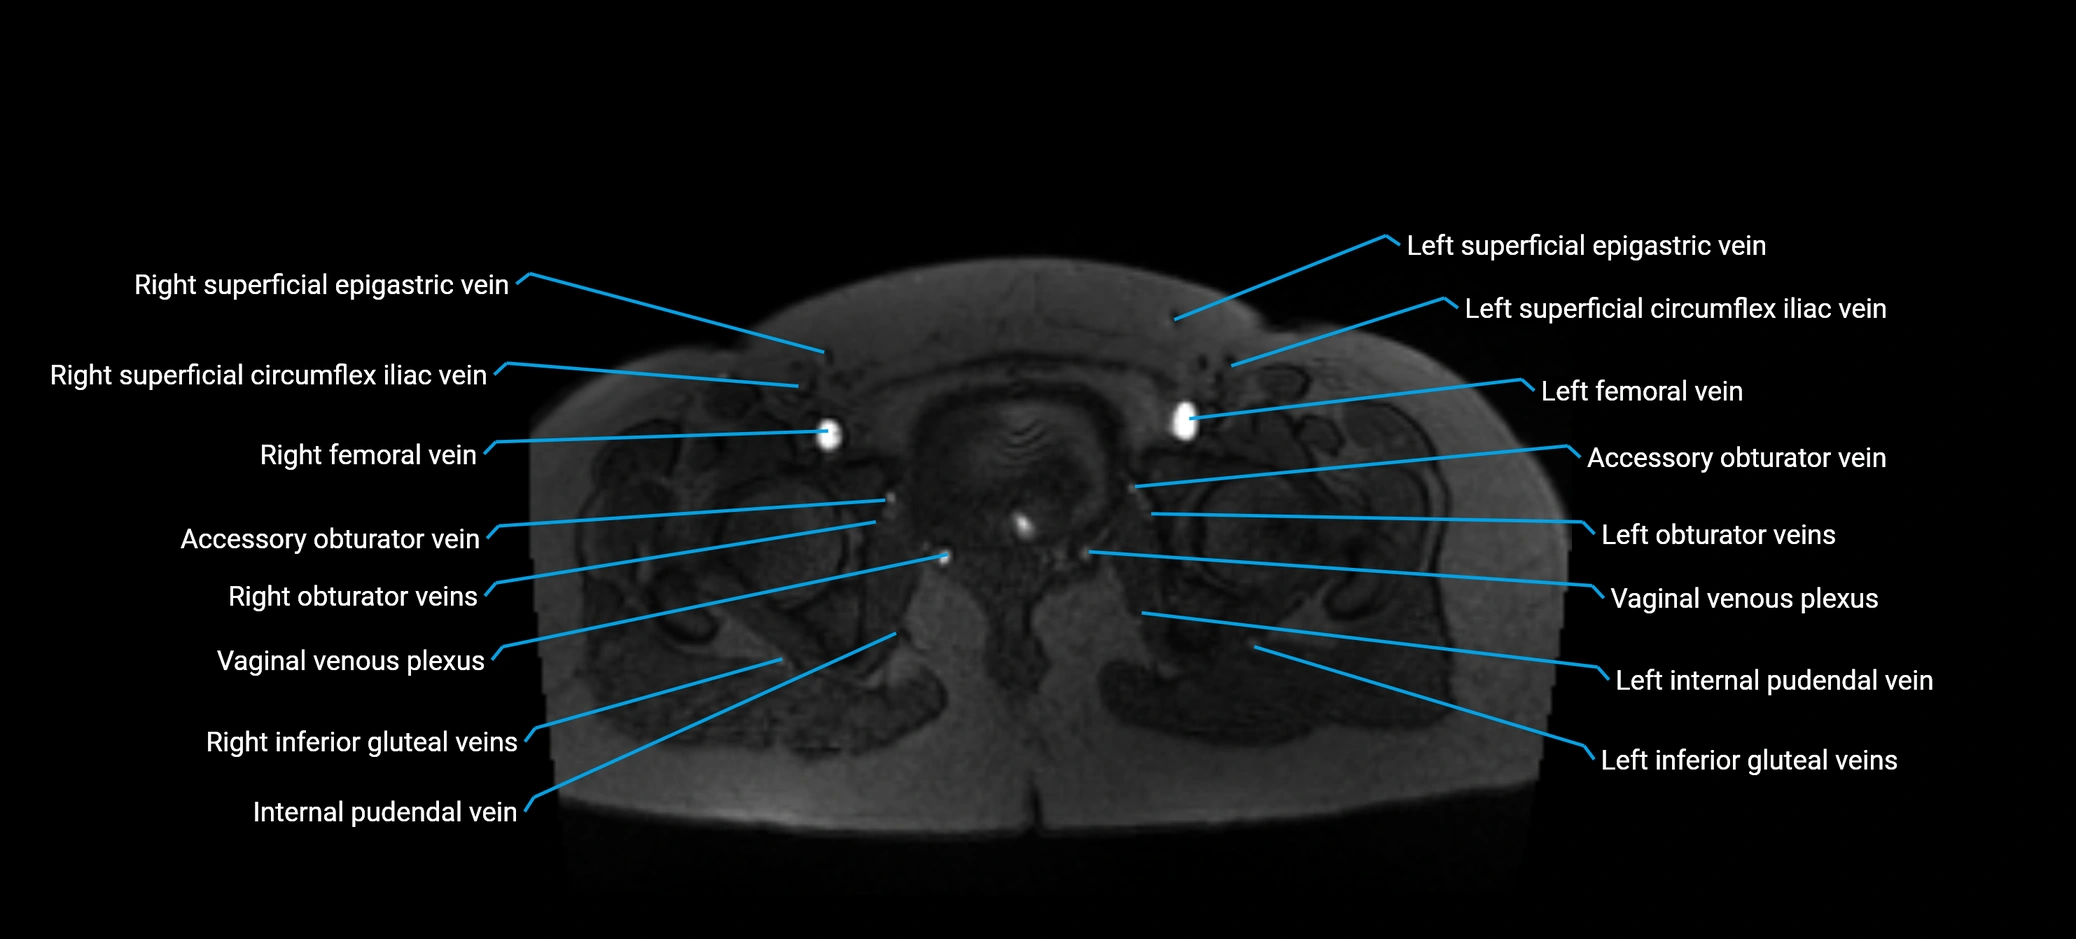

MRI image

image